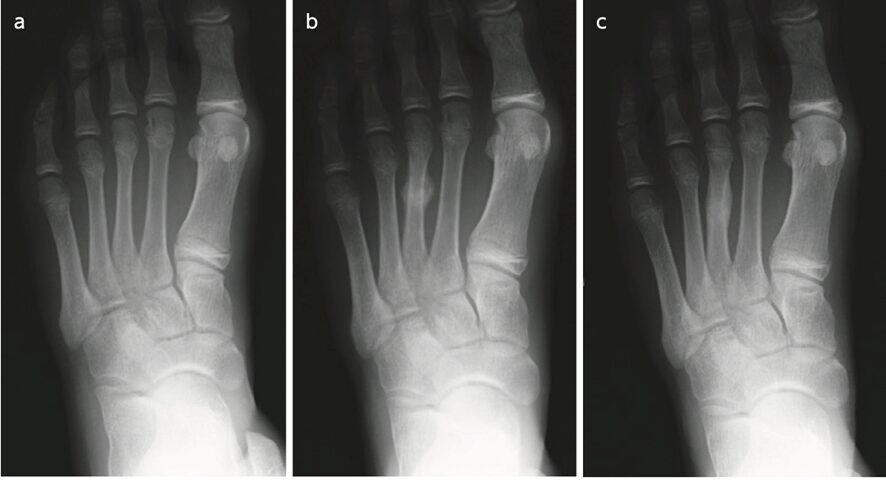

(中学生男子に発症した第3中足骨疲労骨折)

(a.初診時/b.2週間後/c.3ヶ月後)